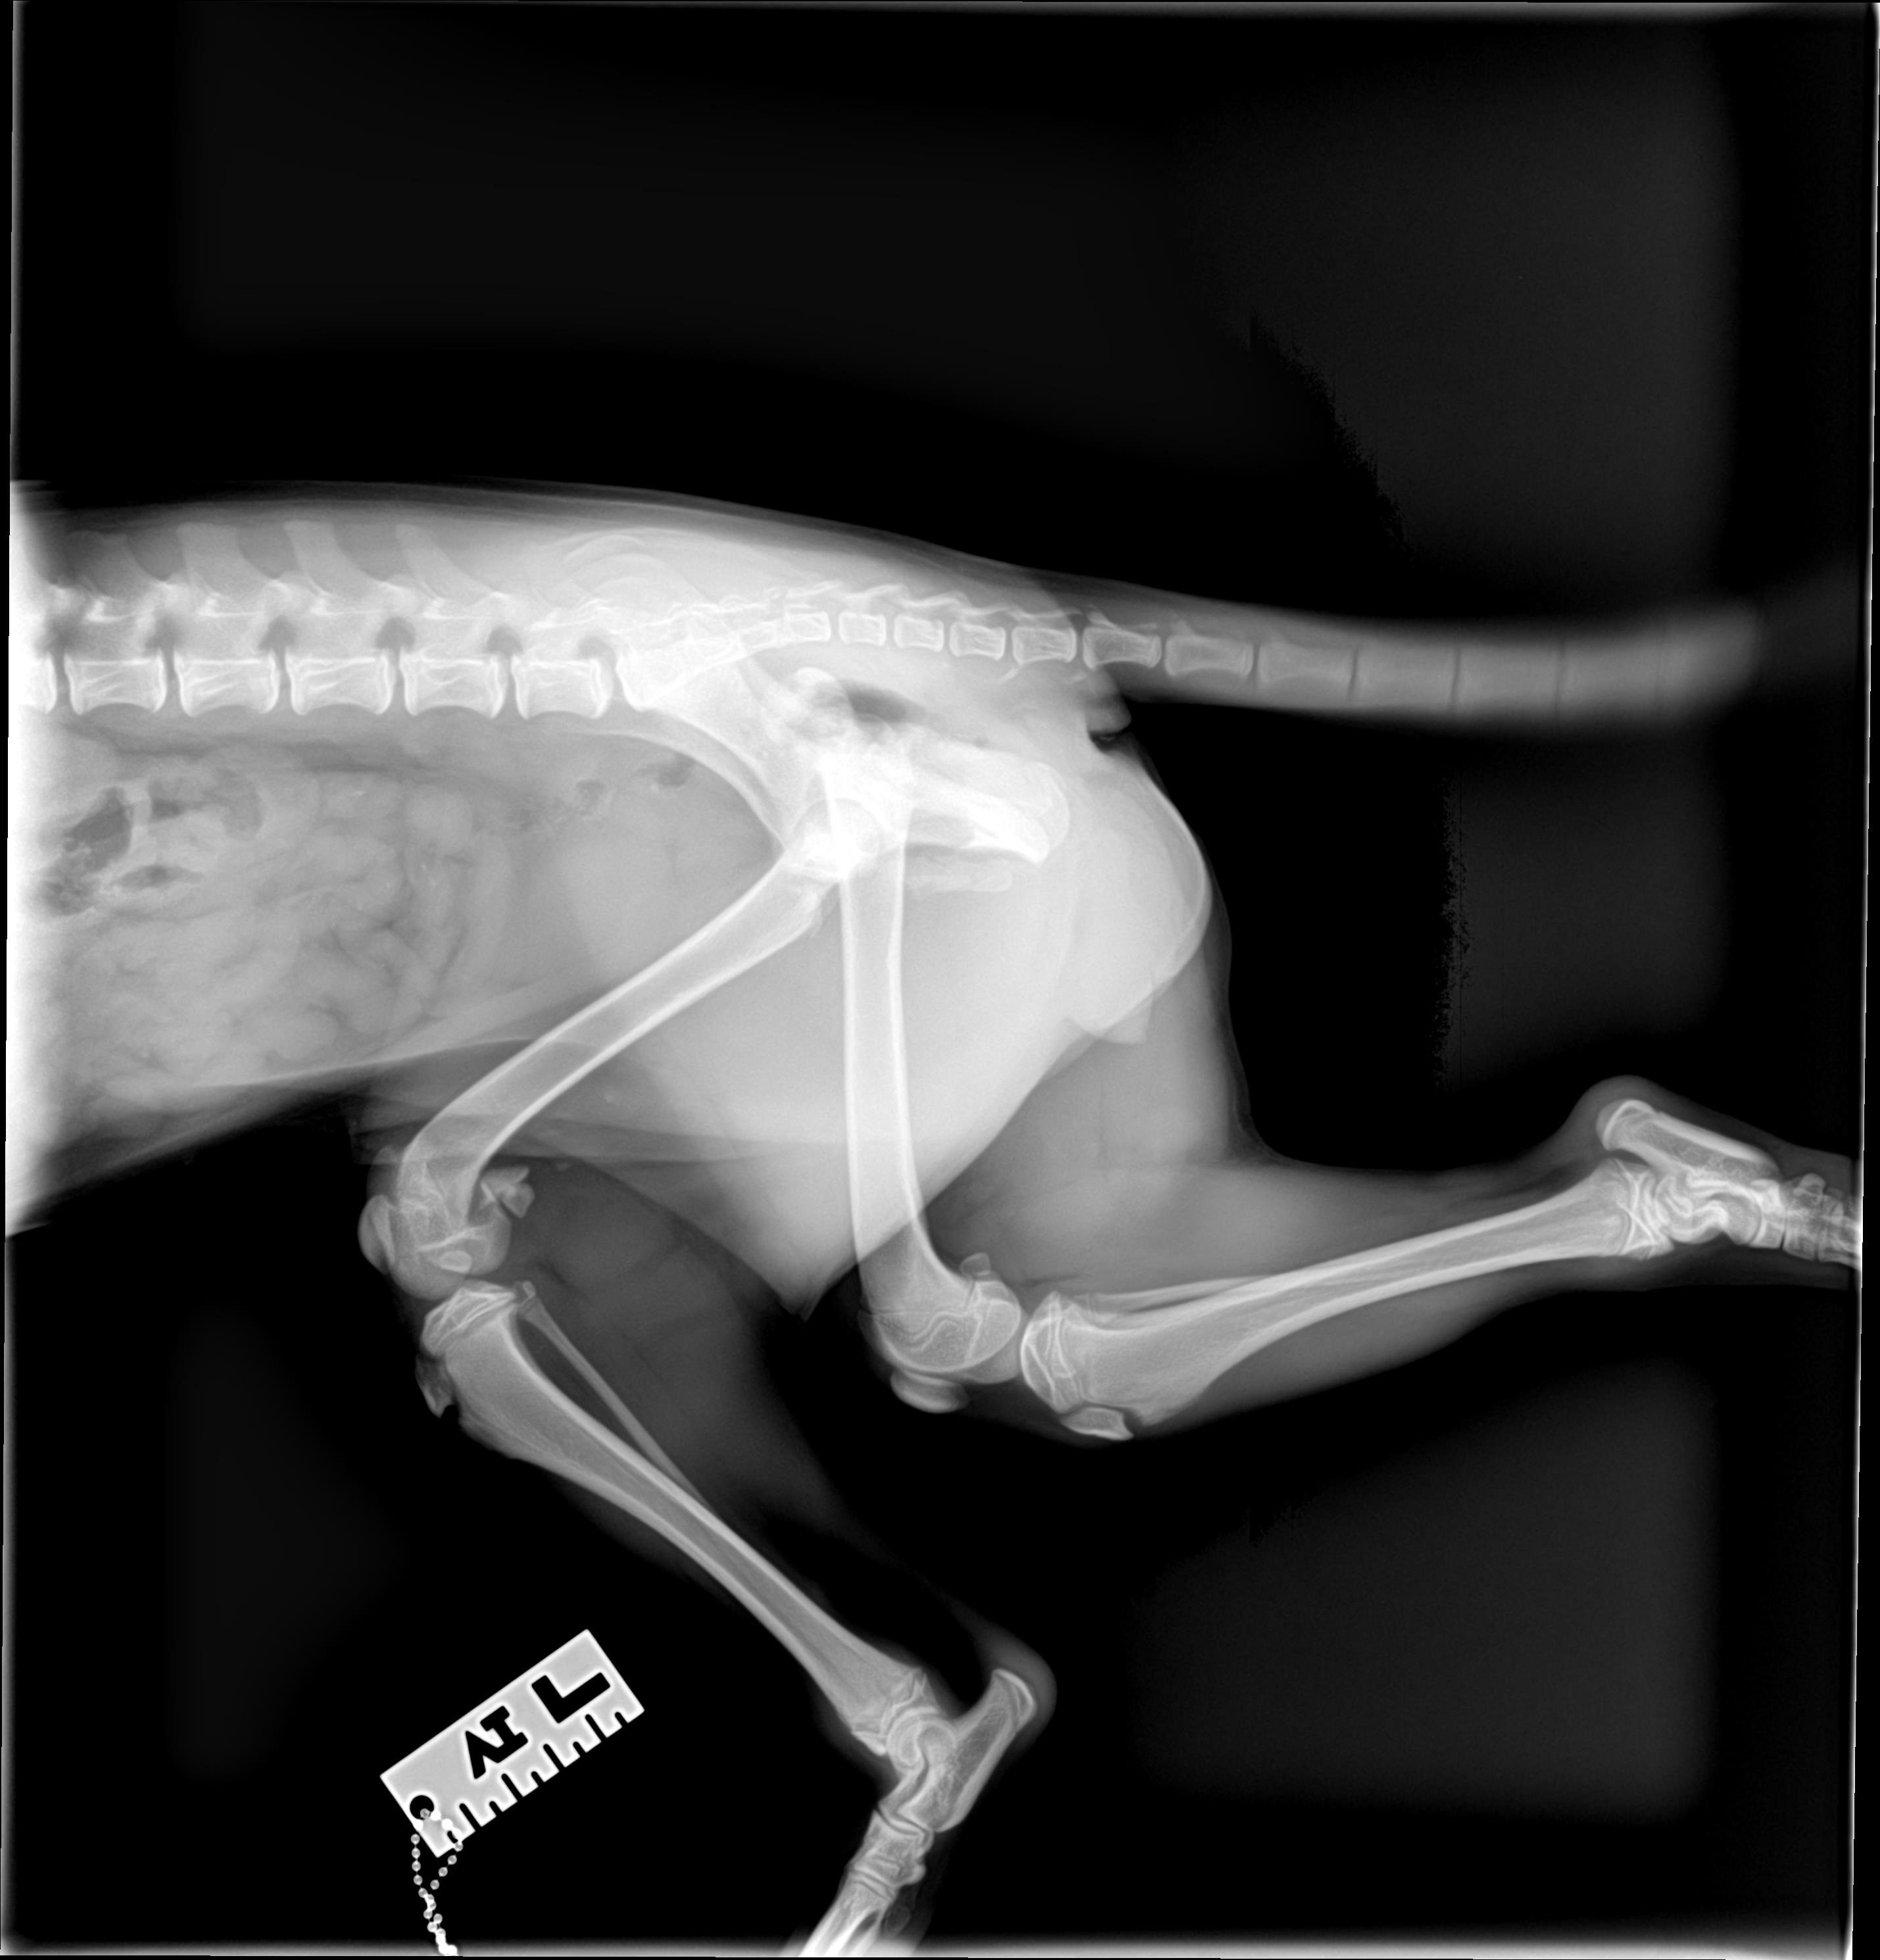

After consulting with our veterinarian, we learned that one surgery (on her hip) is a standard procedure with an excellent recovery outlook. The second surgery is much more complex. The bone in her back leg has already started healing in the wrong position, which means she needs a board-certified orthopedic surgeon to correct it and prevent permanent deformity and lifelong pain.

Once Daphne was safely in our home, our veterinarian examined her injuries in more detail. He confirmed that while her hip surgery can be performed locally, her damaged knee must be corrected by a veterinary orthopedic specialist. It’s a costly procedure but it’s the only way she’ll be able to live a comfortable, active life. We’re doing everything we can to give her the future she deserves, but we need financial help to make it possible.